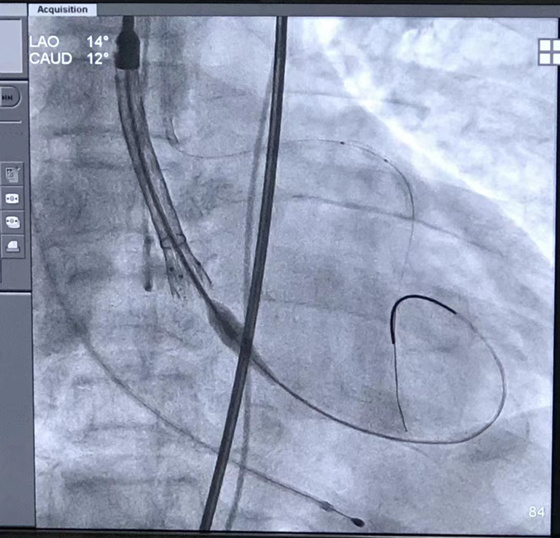

家住张家界慈利县66岁的金奶奶,8个月前出现了胸闷、气促的情况,后多处求医...